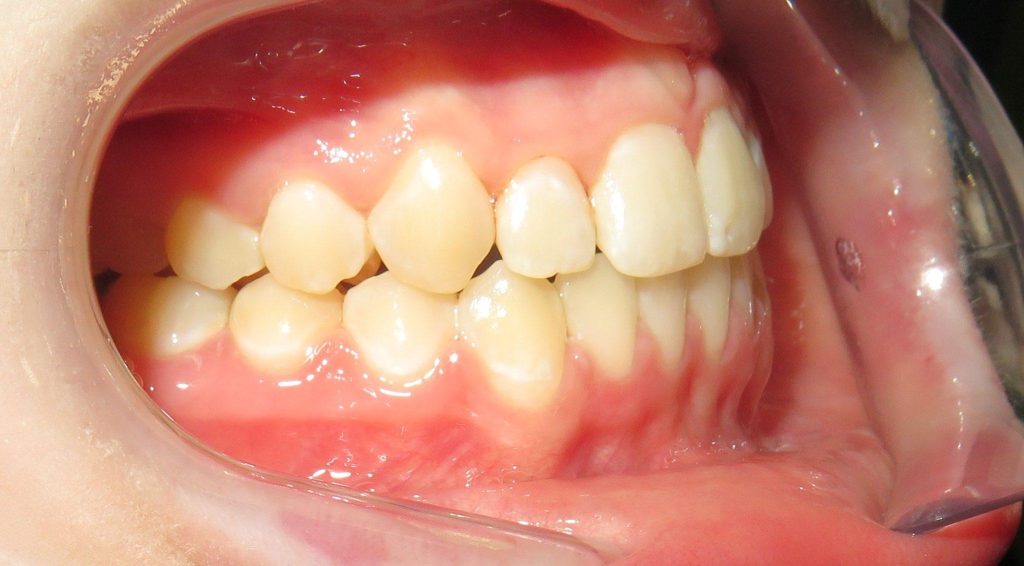

zwężone łuki zębowe,

tyłozgryz,

głęboki zgryz,

stłoczenia,

zrotowane i starte zęby

Pod opieką Agnieszki Łukowicz, Master of Science Orthodontics została poddana zaawansowanemu leczeniu aparatem stałym ligaturowym, Dzięki czemu udało się osiągnąć znaczące zmiany:

poszerzenie luków zębowych,

korekta tyłozgryzu,

rozwiązanie stłoczenia,

odrotowanie zrotowanych zębów,

odbudowa startych zębów.

Efekt estetyczny został dopełniony przez wybielanie zębów i odbudowę kompozytową wykonaną przez dr Monikę Niewitecką.

Przedstawiamy piękny i zdrowy uśmiech naszej Pacjentki!